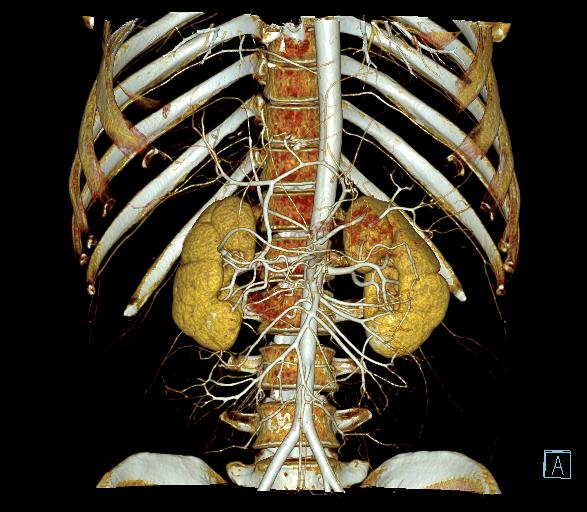

目前在胆管结石、肝脏肿瘤、胰腺肿瘤的精准化手术方案制定与虚拟手术路径方面有着无可替代的作用。其特点是一次一体化扫描成像可获得多重肝脏病变及周围组织、动脉、静脉等信息,通过三维重建技术(VRTMPRCPRMIPMINP)可获得肝动脉、肝静脉及肝门脉重建图像,所获得的数据可创建3D可视化图像,并可虚拟仿真手术,将肝脏、胆道、血管、肿瘤等目标直观、准确、快捷的分离,为精准手术提供前期评估,减少术后并发症,为患者尽快康复提供更为有力的保障。

图1成像方式是目前大多数医院常规采取的扫描方式,满足对疾病的诊断,我中心当前采用的也是此类扫描方式,主要适用于常规检查、诊断,临床需求不单纯是提供诊断、还需要了解病灶与比邻组织器官关系,尤其是与大血管间的关系,制定最优化的手术方案,更快捷、安全、有效的进行手术治疗,但普通扫描在血管区分上欠佳。图2-9为肝脏CT一体化成像图,能更好的区分肝动脉、门脉、胆总管等结构,加上延迟扫描对正常组织器官及病变的显示影响有限,结合3D可视化图像,为临床医师手术提供精准化的参考、制定精准化的手术路径,为患者减少术后并发症。

6:肝动脉VRT

7:肝脏3D可视化

8:肝脏3D可视化

9:肝脏3D可视化